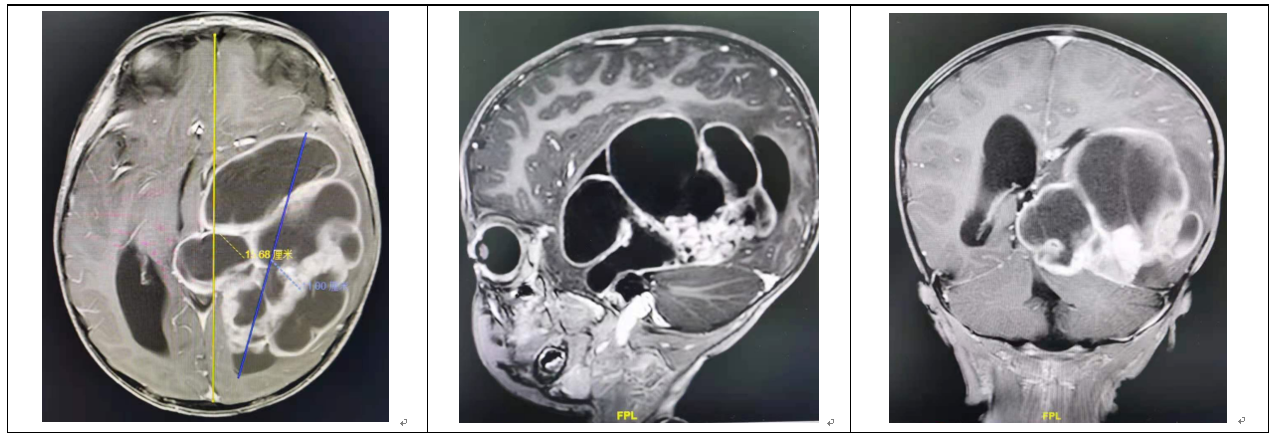

5月14日,王翦带领的外科团队、赖洁兰主治医师为主的麻醉团队、周怡主管护师为主的护理团队,组成10人手术团队,为小烨进行了“左侧颞顶枕叶巨大肿瘤显微切除术”。王翦精心设计了4厘米大小的皮层切口,将盘踞在小烨脑内的巨大肿瘤全部切除。术中出血仅100毫升,术中小烨生命体征稳定。

术前MR(上图):头的最大直径15厘米,而肿瘤直径达到了惊人的11厘米

术后MR(下图):肿瘤被全切除,脑干也复位了

当天下午五点左右,手术结束后半小时,小烨苏醒过来,举起双手,开口就呼唤“妈妈”。术前担心的言语和肢体活动功能受限等情况,都奇迹般地避免了。